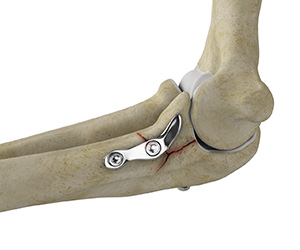

Elbow Fracture Reconstruction

Elbow fracture reconstruction is a surgical procedure employed to repair and restore the appearance and full function of a damaged elbow caused by severe trauma or injury.